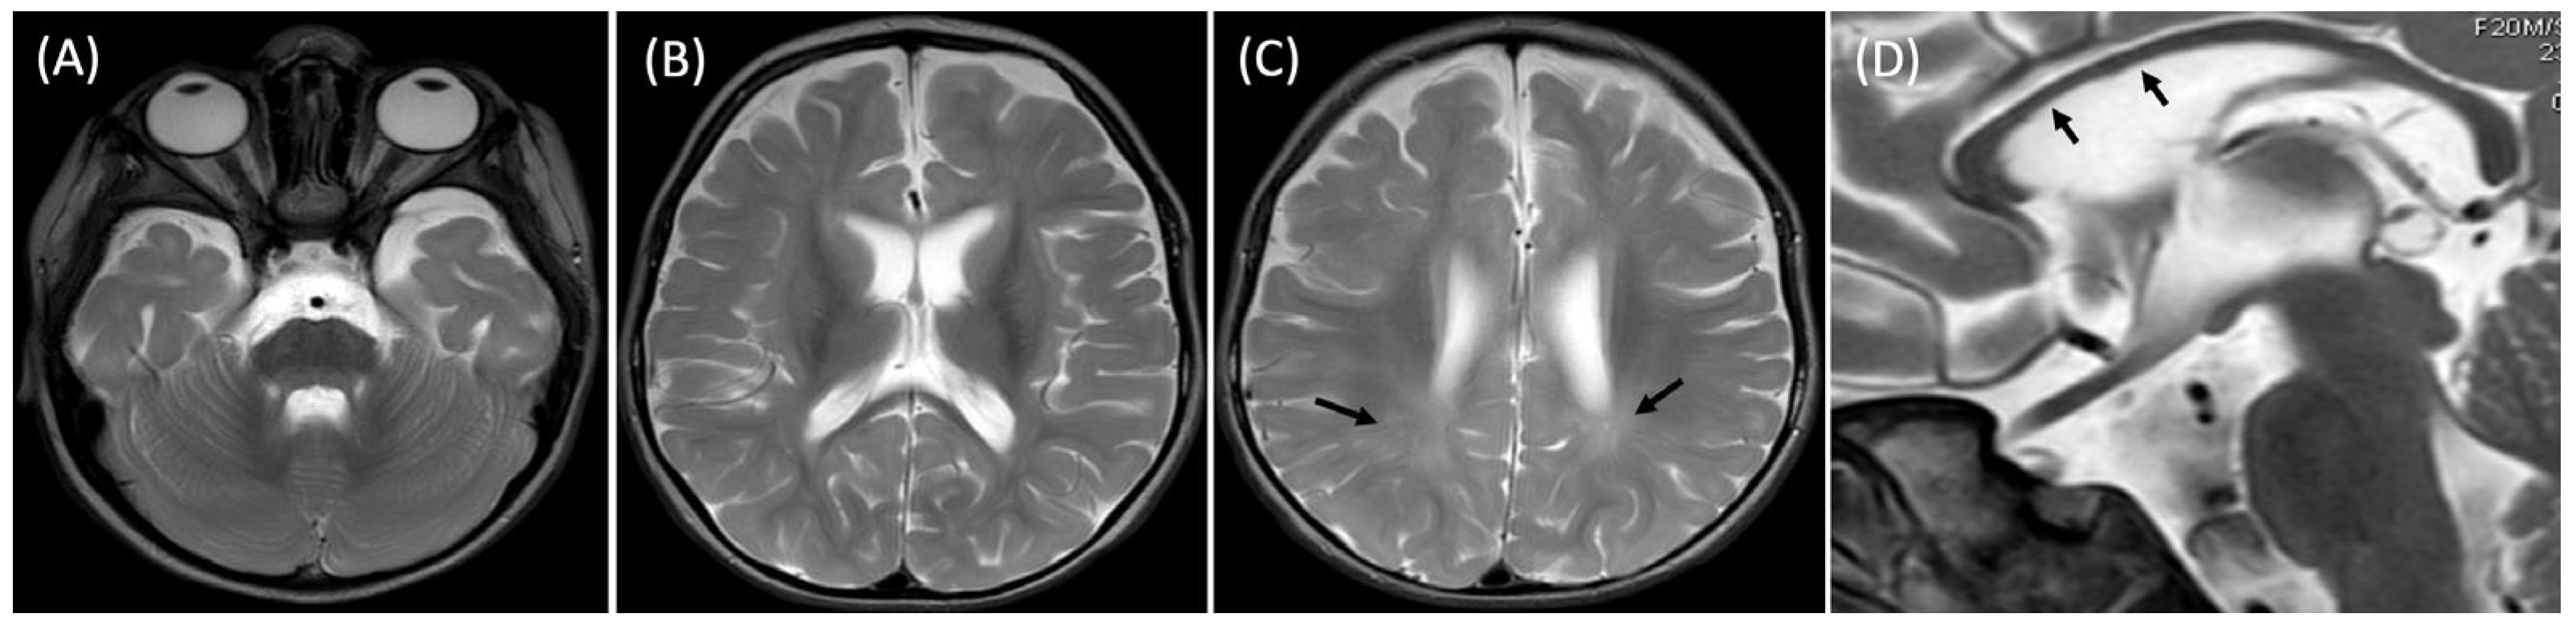

Psychomotor development assessment according to the Vojta neurodevelopmental diagnostics method was conducted at a calendar age of 14 months. In the initial phase of the study, the patient was wearing hearing aids. She established short-term pattern contact with the diagnostician, and occasionally babbled. The patient is unable to turn independently from a supinated position to lying on her front, does not show any desire to grab. Quantitatively, the girl presents patterns from around the completed 12th week of life, trying to build a stable position of lying on her back (Figure 1A). Qualitative deviations that make it difficult for the patient to resist gravity in lying on her back and front are associated with reduced muscle tone in the center, which is manifested by hyperabduction of constantly passively flexed hip joints, flexion of the knee joints, and a tendency to pronate the feet in the lower ankle joints (Figure 1B). The patient tries to bring both hands to the midline, but does not yet do it under visual control. She is able to briefly follow the stimulus by rotating her head to a limited extent to both sides, with a greater range of rotation to the right, which also affects the more intensive loading of the right side, with its elongation in the supine position. In the frontal position, the patient is unable to independently obtain support functions, straightens the shoulder joints, flexing and relieving the elbows. Assisted and after reflex locomotion therapy, she briefly maintains support independently. In the frontal position, the rotation of the cervical and thoracic spine is also expressed to the right, which affects the asymmetric distribution of body weight, with more intensive loading of the left side of the body (Figure 1C).

In seven postural reactions of the body in space according to Vojta, the patient presents a persistent Moro reflex in six of the seven postural tests, with dominant hyperabduction in the hip joints and an extension tendency of the cervicothoracic segment of the spine, together with right-sided rotation (Figure 2B–G). Only in the first suspension (traction) test does the patient show a partial, age-appropriate flexion response of the head and cervicothoracic spine, opposing gravity by activating the ventral neck and thoracic muscles; in the lower limbs, excessive abduction, hip and knee flexion, and foot pronation remain constantly visible (Figure 2A).

Figure 1. Delayed spontaneous motor skills of the patient in the supine position (A), with a constant tendency for lateral flexion and rotation to the right, also in the prone position (C), with excessive flexion and abduction in the hip joints and pronation of the ankle joints (B).